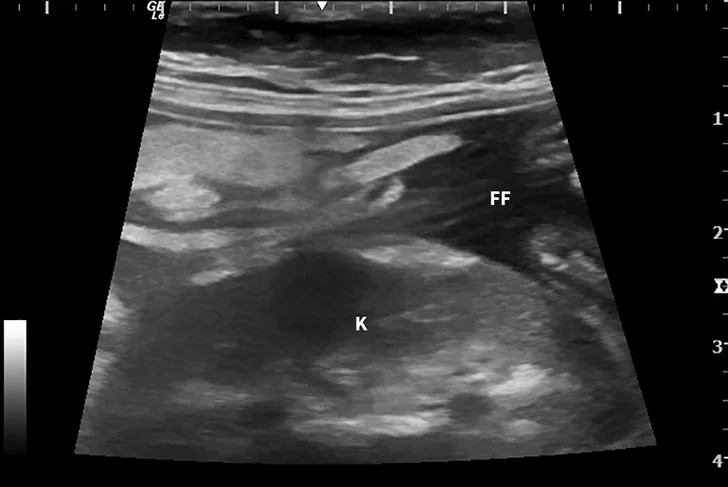

Abdominal ultrasound images from a cat.

FIGURE 1

Ultrasound image showing abdominal effusion in a cat with wet FIP. Anechoic fluid is present between organs, distending the abdomen. FF = free fluid; L = liver; S = spleen; K = kidney